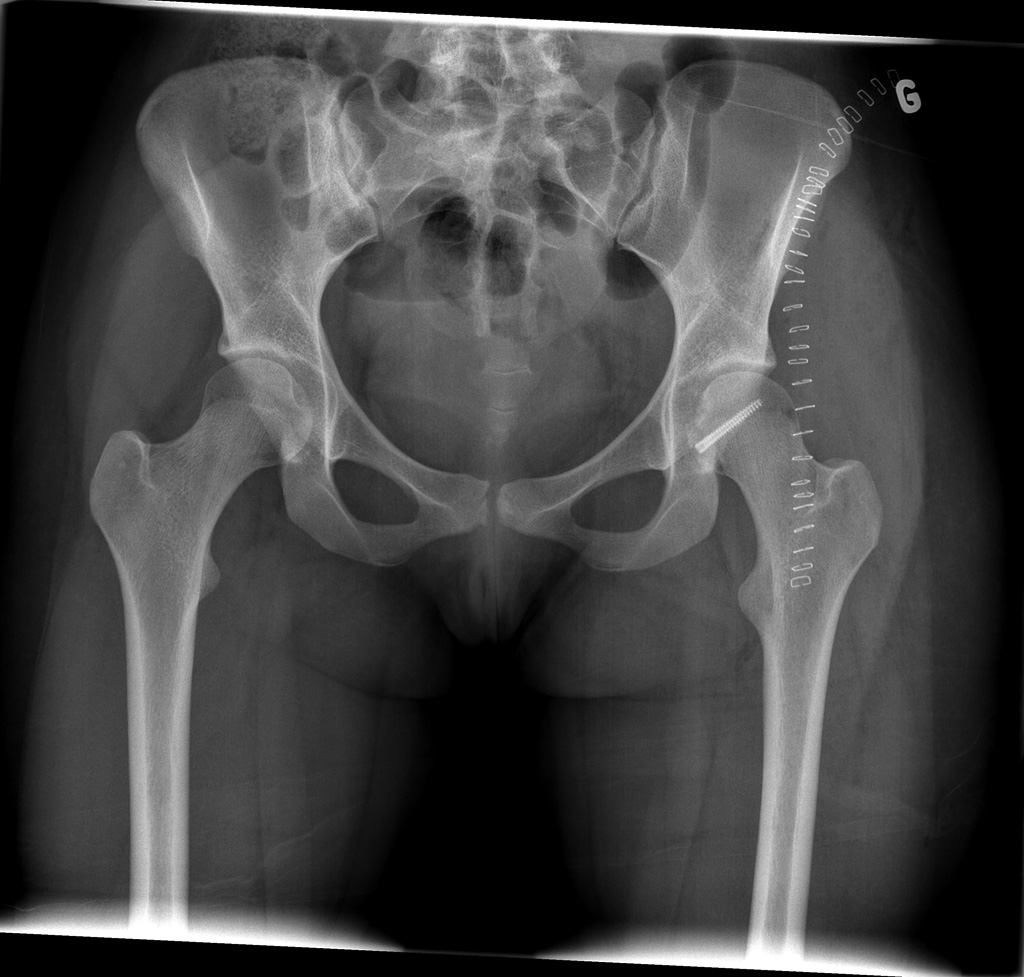

16-year-old female:

Postoperative control of a fracture-dislocation of the femoral head.

Screw

Plate and screws

Post reduction status of a femoral head fracture-dislocation with screw fixation of the bone fragment.

Staples

Metallic staples for skin closure.